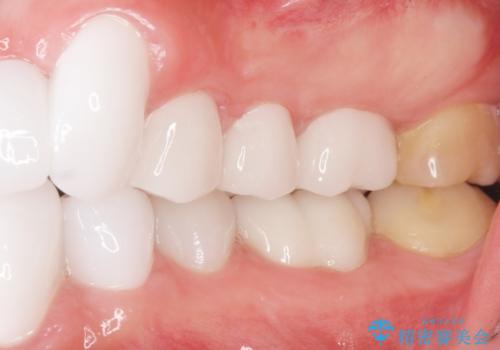

矯正治療とホワイトニングを提案しましたが希望されず、「接客関係の仕事で矯正治療は考えられない、短期間で治療を終わらせたい、ホワイトニングでは難しい位の人工的な白さにしたい」とのご要望により、治療前にワックスアップ模型を作製し何度もコンサルテーションを重ね、治療方針を決定しました。

歯頚ラインが変えられないことや天然歯を削るリスクをご理解頂いた上で、オールセラミッククラウンによる補綴治療を行いました。(見えない奥歯のみ天然歯のままとしました)

クラウンの色味に関して、自然な白さ(シェードA1~NW0.5)のクラウンを作製・試適したところ「もっと白くしたい」と希望され、当院で最も明度の高い色(シェードNW0)に修正しました。

被せ物の種類:オールセラミッククラウン スタンダード (シェード:NW0)